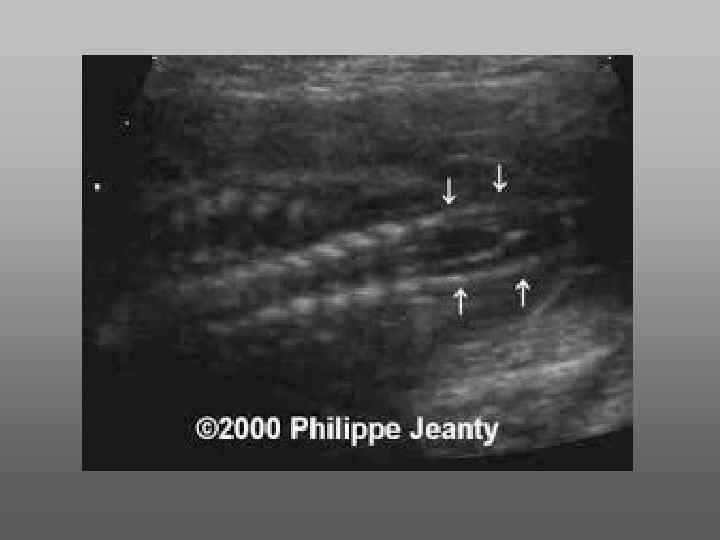

Диагностика • При осмотре позвоночника – осмотр задних центров оссификации. В норме они расположены параллельно другу или под незначительным углом.

При Spina bifida возникает U или Y – образный дефект

Небольшие дефекты чаще диагностируются при тщательном осмотре в поперечной плоскости